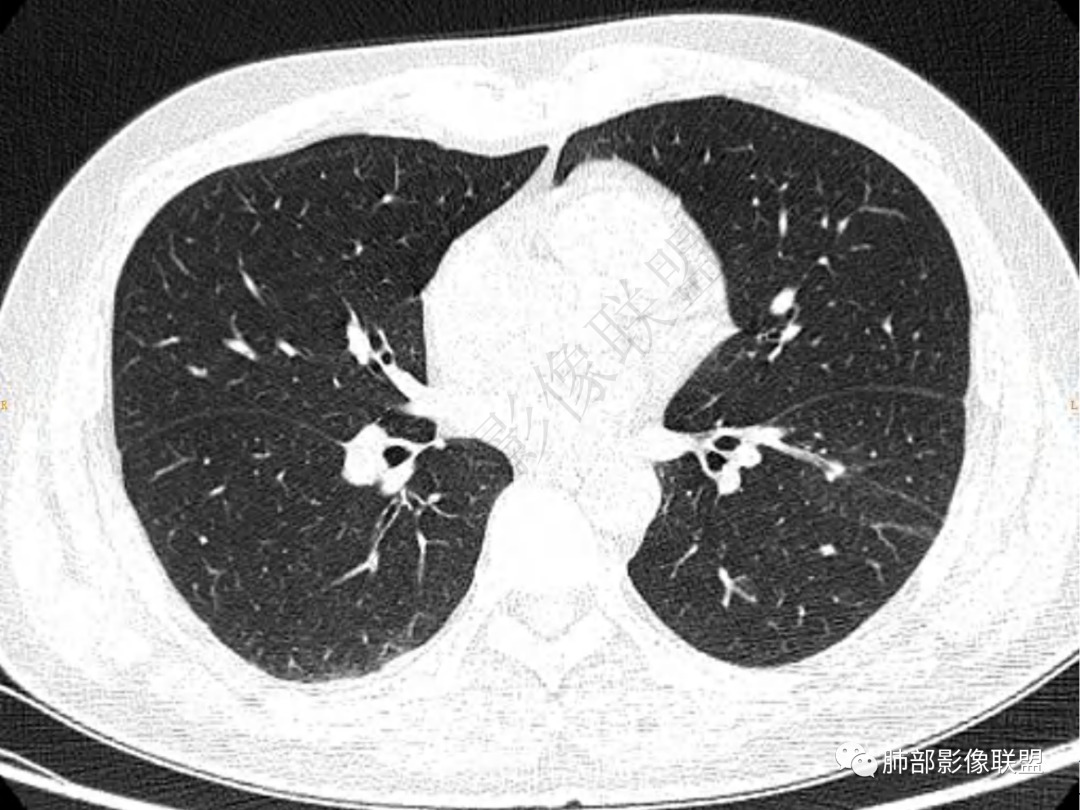

2.左肺下叶团片影,跨背段及内前基底段,实性部分类椭圆形,密度不甚均匀,可见毛刺及棘状突起,未见典型分叶及胸膜凹陷。病灶上下缘可见相应肺段支气管旁进侧出,管壁轻度增厚,未见狭窄阻塞。

3.周边较大范围磨玻璃影,边界相当模糊,小叶增厚明显。注意叶裂另一侧、左肺舌段亦可见磨玻璃影及增厚的小叶间隔。未见明确卫星病灶。

4.实性部分不均匀环形强化并显示一小范围低密度坏死区或空洞。较之肺窗,整体纵隔窗范围较小,提示病灶并不十分密实。抑或为不同时段图像。

1.病灶不够密实,没有典型分叶,收缩乏力等,支气管未见截断等,缺乏一般肿瘤性肿块特征。

2.周围磨玻璃影边界不清缺乏限制,甚至“激惹”到相邻肺叶,也许提示较明显的炎性水肿。